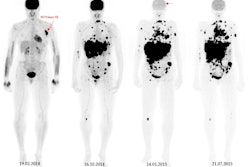

Melanoma is the third most common metastatic tumor to the brain and accounts for around 10% of all developed brain metastases, and while F-18 FDG-PET/CT is accurate for detecting melanoma metastases, data on its baseline prognostic value are scarce, Austrian authors write. They investigated the technique's value in predicting brain metastases in patients with proven melanoma.